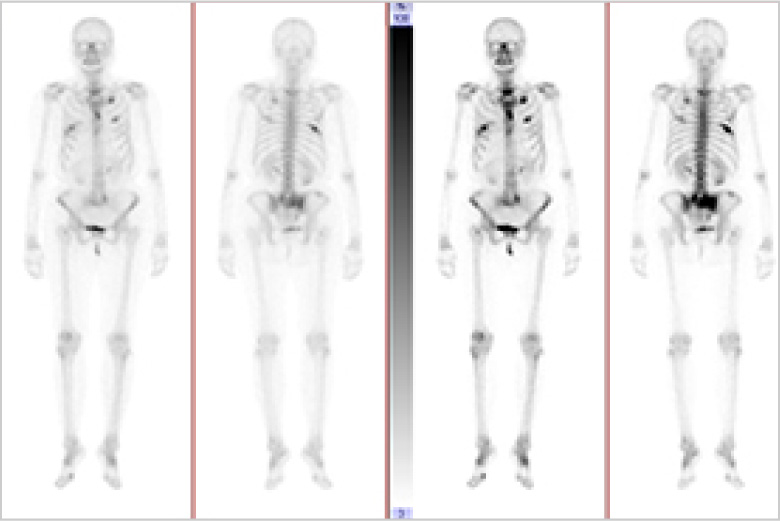

RI(核医学検査)

RI検査(核医学検査)は、ごく微量の放射性物質(ラジオアイソトープ:RI)を含む薬を用いて病気を診断する検査です。この放射性医薬品を注射、吸入などにより体内に取り込みます。体内に取り込まれると、特定の臓器(骨や腫瘍など)に集まりそこから放出される放射線(γ線)をガンマカメラで測定し、その分布を画像化します。

この検査の特徴は臓器の位置や大きさの他に機能が分かるというところです。

検査の種類

心筋血流シンチ 脳血流シンチ 骨シンチ 甲状腺シンチ 腫瘍シンチなど

骨シンチ

転移性骨腫瘍